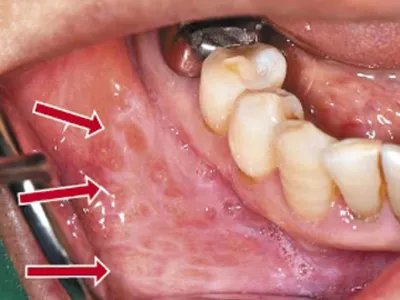

扁平苔藓在口腔内侧的黏膜上表现为形状不规则的白斑样膜状物,由多个条状白斑相互融合形成,整体形态与烧伤后出现的瘢痕类似,微隆起于患处正常黏膜,边界清晰。扁平苔藓腘窝斑图